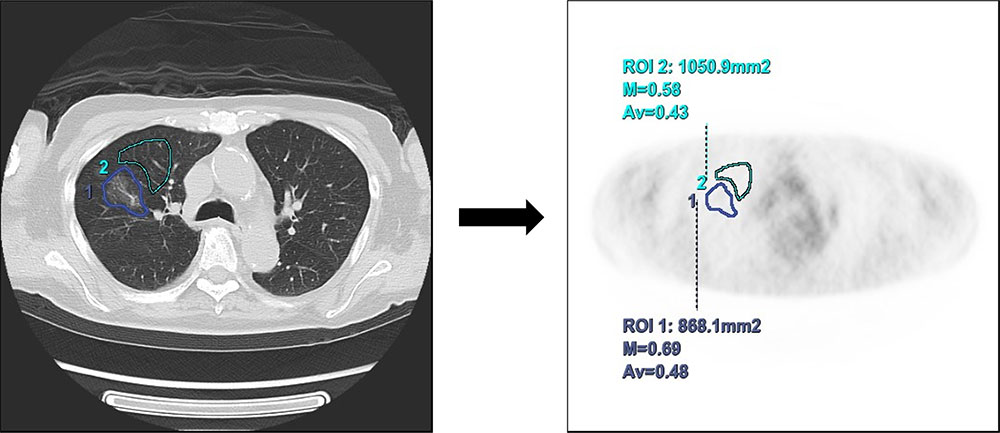

従来の装置ではこのような肺野の微細な病変に対しては、CT画像上で確認できる病変部に対してROIを設定し、その周辺に正常部位のROIを設定することによってSUVを比較して読影医に画像を提供していましたが(Fig.3)、この方法では呼吸によるズレなども考慮するとPET画像上で正しいROIを設定できているのか判断に迷うことが多くありました。本症例ではPET画像上で直接SUV測定を行う事ができ、自信を持って読影医に画像を提供でき、高分化腺癌の可能性否定できずという結果になりました。

Fig.3 従来の測定の仕方。

CT上にROIを設定→PET画像上でSUV測定し、病変部と正常部にSUVの差があるかを確認。